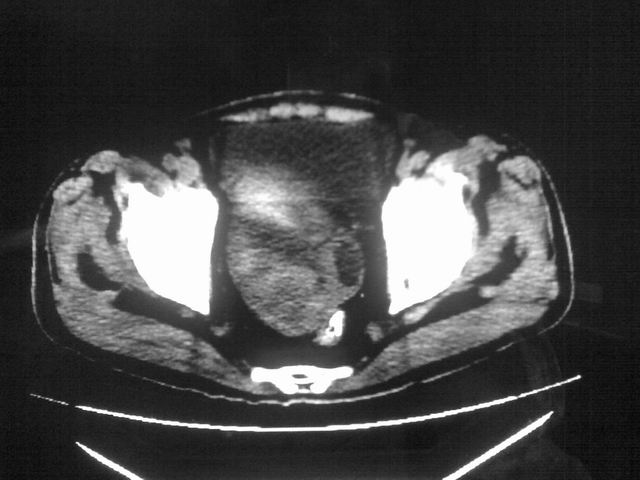

患者m 56岁,盆腔及下腹部胀痛半年,加重1月余,消瘦\中重度贫血.(附:平扫时直肠的高信号为,残留的钡剂).补一下病史:胃镜及纤维结肠镜均无明显异常.

膀胱后方及直肠前方见巨大混杂密度影,与前列腺相连且向膀胱内突入,精囊腺显示不清;考虑前列腺癌侵犯精囊、膀胱。

膀胱及直肠间有不规侧的软组织密度影,内密度不均匀。其内有坏死囊变,前列腺及精囊腺,膀胱后壁受浸。结合病史考虑腹膜后肉瘤可能性大。